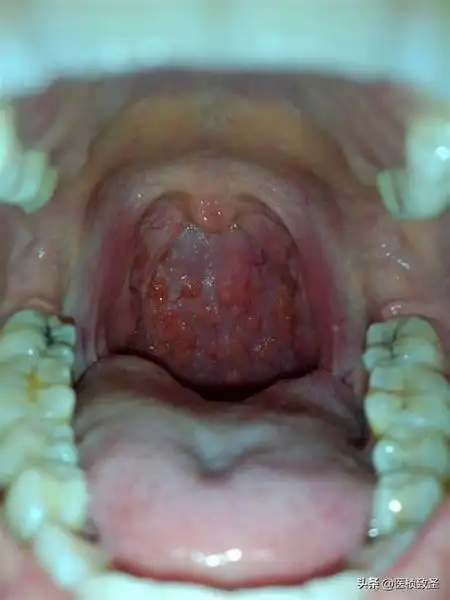

小孩嗓子老感觉有东西,老吭吭的怎么办? - 石塘网